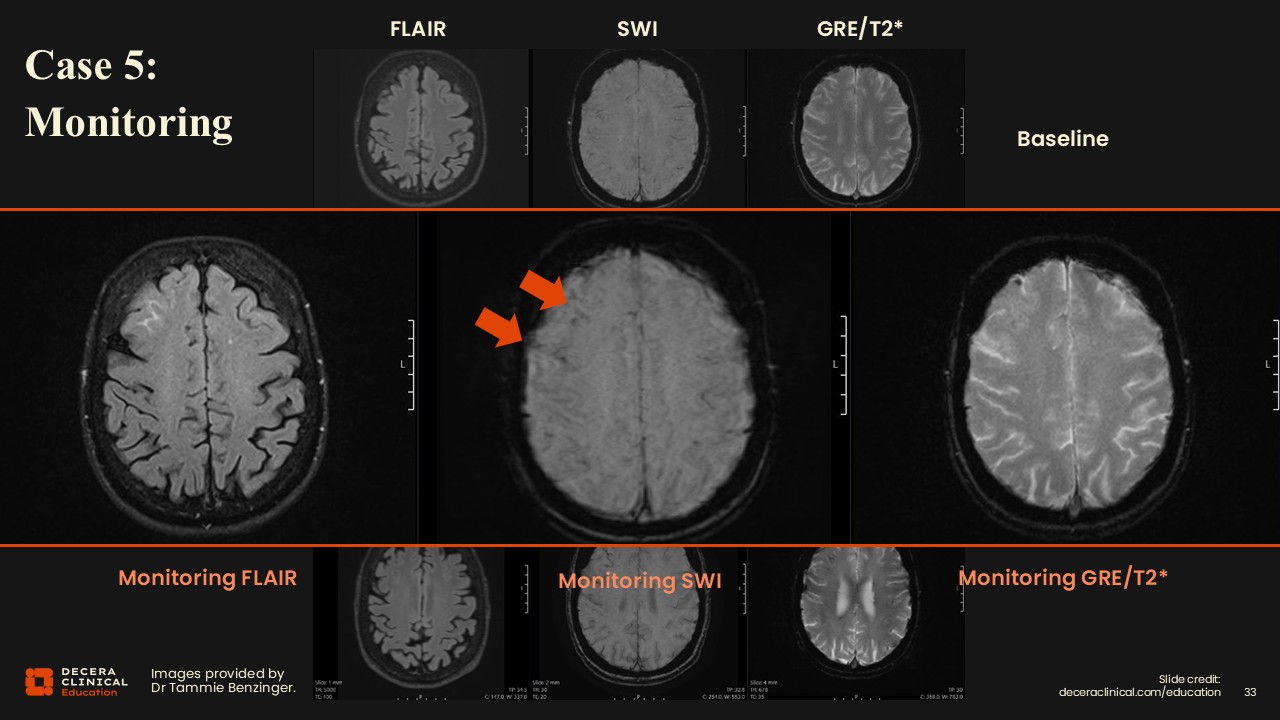

Case 5: ARIA Monitoring in Comparison with CT Scan

Dr Benzinger:

In this case, vasogenic edema in the right frontal lobe becomes more visible in the enlarged image.

Case 5: ARIA Monitoring and CT Scan

The trick is that there is also a little bit of signal loss on SWI, and comparison with baseline confirms that these are not just veins in that area, but this represents new change.

Case 5: ARIA Monitoring (Grading)

For classification, this is consistent with mild ARIA-E along with new susceptibility signal loss indicating additional microhemorrhages, graded as moderate ARIA-H based on lesion count. The plan would be to place a phone call to the clinical treatment team, correlate for symptoms, and recommend a follow-up scan.